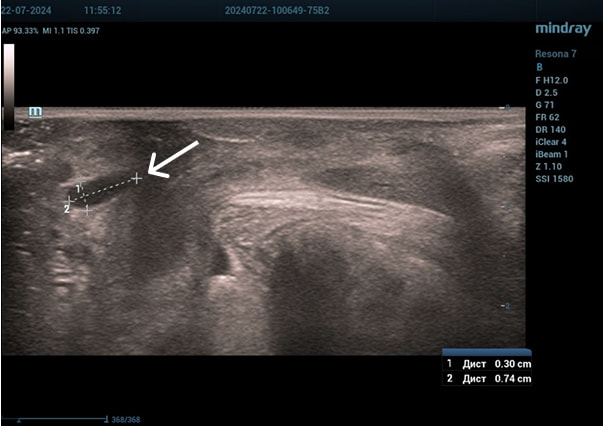

Трансперинеальный доступ, линейный датчик.

Слева от уретры округлое образование с четкой капсулой и мелкодисперсной взвесью размерами 1,5×1,0 см (филлер с воспалением), справа — анэхогенное овоидное образование (филлер).

Эхограмма 2